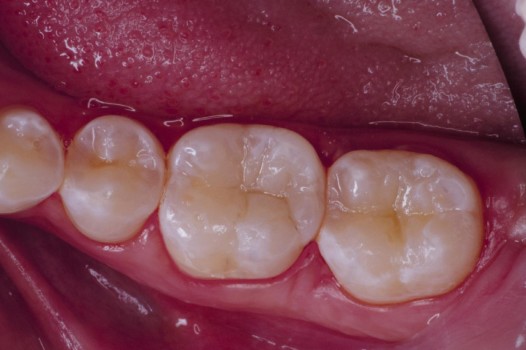

The pits and grooves on the biting surface of teeth often serve as plaque traps and pathways for bacteria to invade the inside of a tooth. This, in turn, leads to the development of cavities. Early diagnosis and treatment arrests the spread of decay and thus prolongs the life of the tooth. Regardless of the size of the affected tooth structure, decay may be swept away with the air abrasion technique and corrected by bonded ceramics, which seal the tooth against further bacterial invasion.